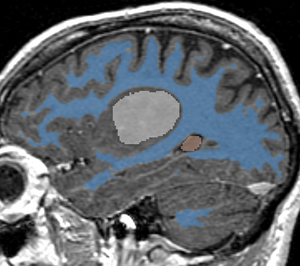

RSS result for Brain MR image

With Intensity Homogeneity set at 0.2, Smoothness at 0.05, and Number of Iterations at 1000, we get the following results:

Segmentation result, axial view

Segmentation result, sagittal view